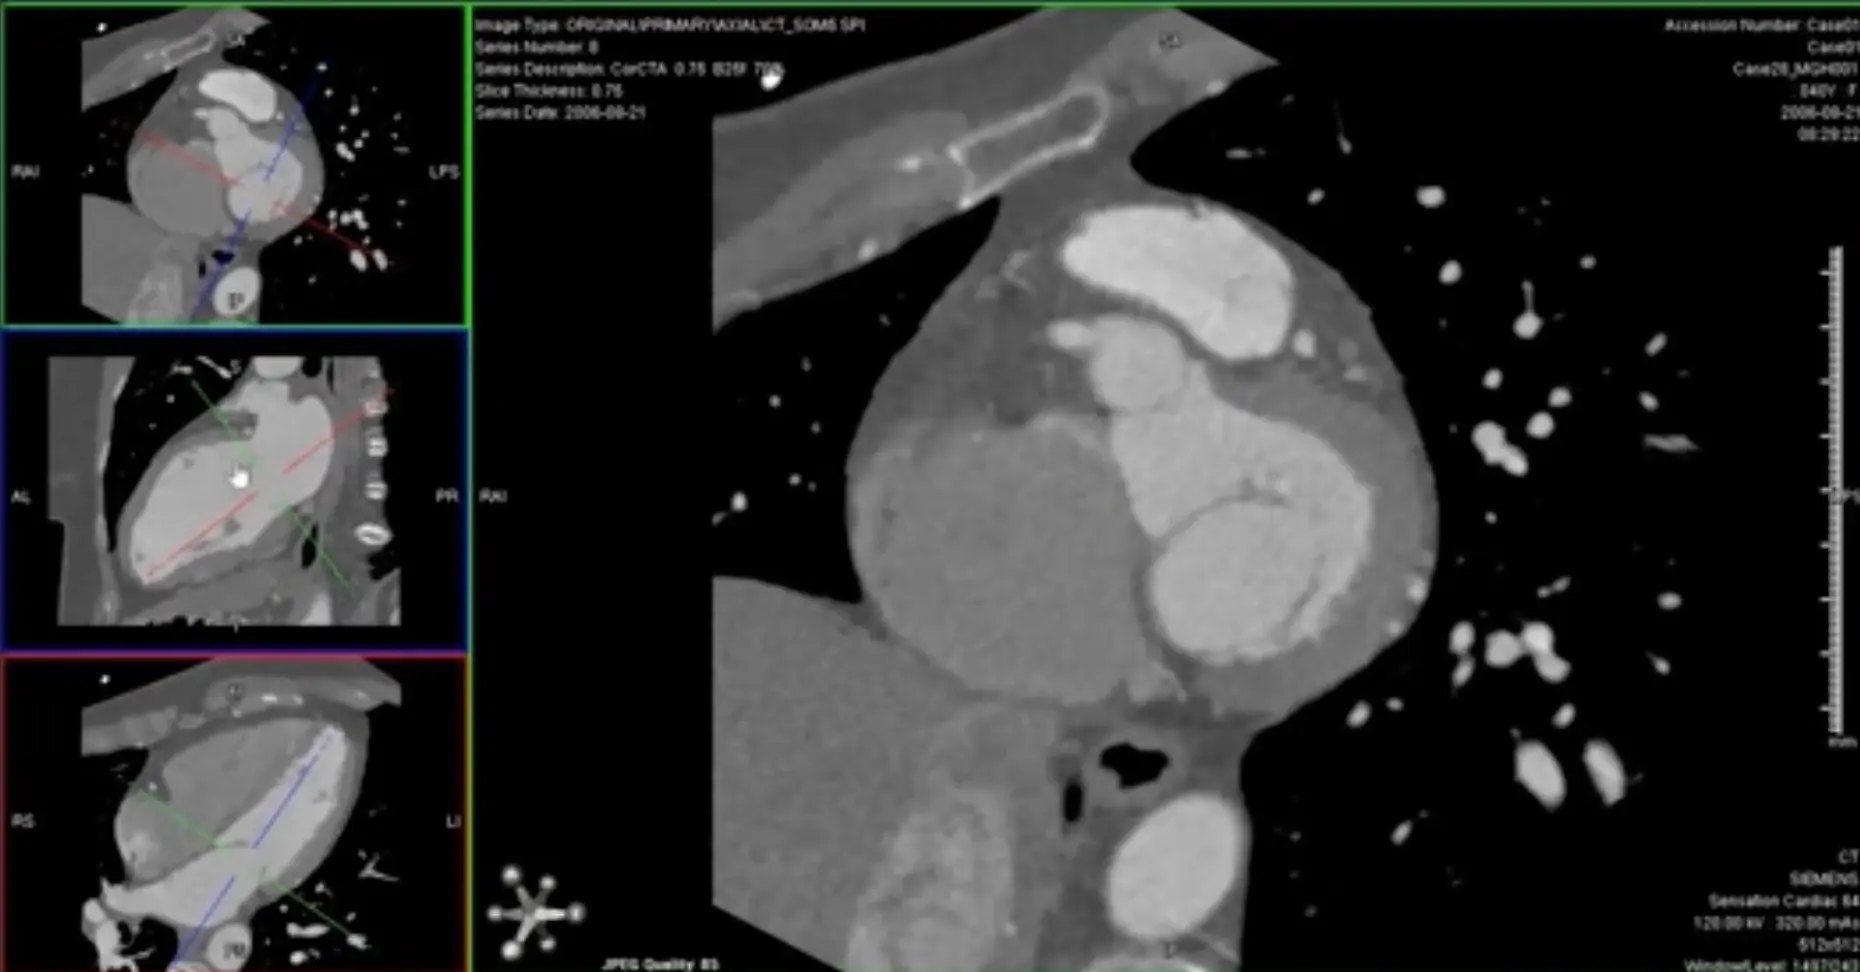

’C’ view of RCA

Useful to view RCA and LCx

Both the RCA and LCx lie along the atrioventricular groove, so the ‘C’ view is useful to evaluate the RCA and LCx. When you get your RCA lined up (as below) in the MIP projection, you can scroll along and assess the LCx as well.

- Switch to MIP view

- MIP will help give you an overview of the vessel. Once you identify some areas of concern → switch to thin-slice images for closer investigation 🔍 and evaluation for stenosis.

- Go down to the thinnest possible section within the MIP view

Avoid assessing diameter stenosis using thick-slab MIP

When quantifying stenosis, you will always want to use thin slice images.